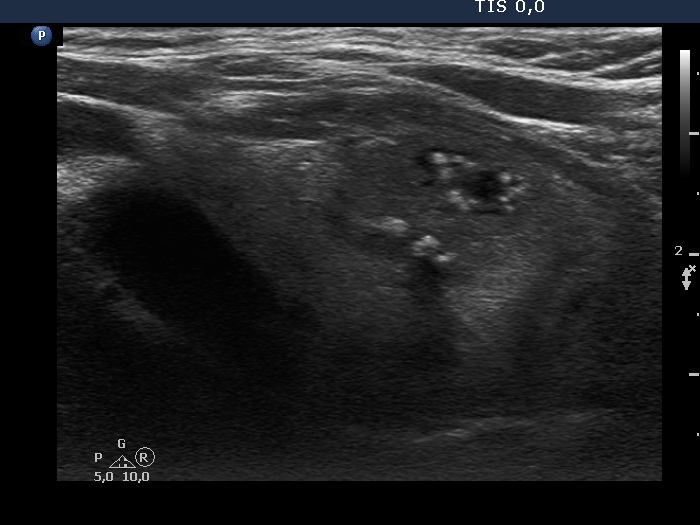

Ultrasonography. The thyroid was echonormal and beside has small hypoechogenic areas, had two nodules. Both were hypoechoic. The lesion in the left lobe presented different intranodular hyperechogenic figures including macrocalcifications and comet-tail artifacts. Some granules were probably microcalcifications.

Comment. It is worth analyzing the presentation of the different echogenic figures in the video. Moreover, three different settings can be compared in projecting the nodule in the left lobe.